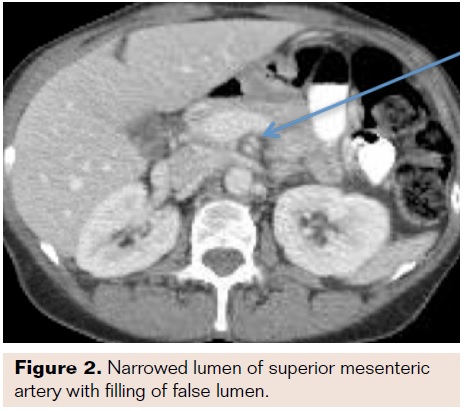

Abdominal exam revealed focal tenderness in the suprapubic region without rebound or guarding. There was no purpura or other abnormal skin findings. Vasculitis workup was not undertaken. A CT of the abdomen was performed, which showed SMA dissection within 1 centimeter from the takeoff and cecal wall thickening without signs of ischemia (Figures 1-3). No other dissection or vascular abnormality was noted. She was admitted to the vascular surgery service, made NPO, and started on a heparin infusion as well as ciprofloxacin and metronidazole for the typhlitis.